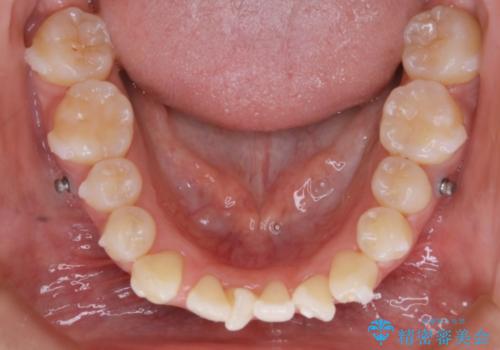

矯正装置の希望がインビザラインだったため、マイクロインプラントを併用し、奥歯から順に遠心移動をかけていくことにより非抜歯でも主訴のガタつきを治すことができました。

マウスピースとマイクロインプラントを組み合わせることで、抜歯をしなくても歯並びを治すためのスペースを作ることができます。奥歯から順に移動させていくので前歯に変化が出るまでには時間がかかりますが、その分健康な歯を抜歯することなく理想的な歯並びを手に入れることができます。